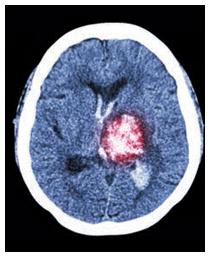

The connection between periodontal status and stroke is examined in “Reducing Stroke Risk.” Lauren Dennis, MHA, BS, and Souvik Sen, MD, MPH, explore the signs and symptoms of stroke, strategies for prevention, and stroke’s association with periodontal diseases. As the oral cavity is connected to the trachea and lower airway, bacteria can travel through this pathway, raising the risk of lung infection. The CE course “The Oral Microbiome and the Risk of Lung Infection” by Frank A. Scannapieco, DMD, PhD, discusses this process and what it means for oral health professionals. Each article offers two CE units.